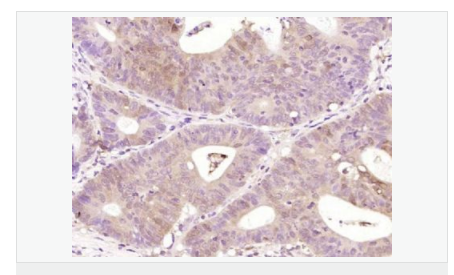

| 產(chǎn)品應用 | WB=1:500-2000 ELISA=1:5000-10000 IHC-P=1:100-500 IHC-F=1:100-500 (石蠟切片需做抗原修復) not yet tested in other applications. optimal dilutions/concentrations should be determined by the end user. |